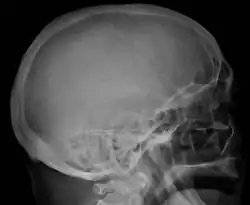

Bone pain affects almost 70% of people with multiple myeloma and is one of the most common symptoms.[2]: 653 [23] Myeloma bone pain usually involves the spine and ribs and worsens with activity. Persistent, localized pain may indicate a pathological bone fracture. Involvement of the vertebrae may lead to spinal cord compression or kyphosis. Myeloma bone disease is due to the overexpression of receptor activator for nuclear factor κ B ligand (RANKL) by bone marrow stroma. RANKL activates osteoclasts, which resorb bone. The resultant bone lesions are lytic (cause breakdown) in nature. They are best seen in plain radiographs, which may show "punched-out" resorptive lesions (including the "raindrop" appearance of the skull on radiography). The breakdown of bone also leads to the release of calcium ions into the blood, leading to hypercalcemia and its associated symptoms.[24]

The diagnostic examination of a person with suspected multiple myeloma typically includes a skeletal survey. This is a series of X-rays of the skull, axial skeleton, and proximal long bones. Myeloma activity sometimes appears as "lytic lesions" (with local disappearance of normal bone due to resorption) or as "punched-out lesions" on the skull X-ray ("raindrop skull"). Lesions may also be sclerotic, which is seen as radiodense.[76] Overall, the radiodensity of myeloma is between −30 and 120 Hounsfield units (HU).[77] Magnetic resonance imaging is more sensitive than simple X-rays in the detection of lytic lesions. An MRI may supersede a skeletal survey, especially when vertebral disease is suspected. Occasionally, a CT scan is performed to measure the size of soft-tissue plasmacytomas. Nuclear Medicine Bone scans are typically not of any additional value in the workup of people with myeloma (no new bone formation; lytic lesions not well visualized on nuclear bone scan).

Skull X-ray showing multiple lucencies due to multiple myeloma -